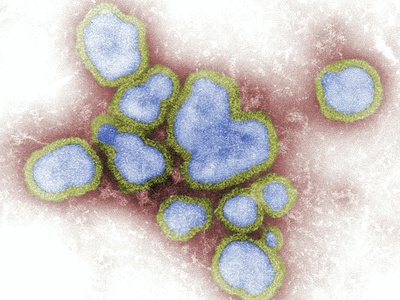

Influenza (Flu)

Seasonal influenza, caused by influenza A and B, leads to fever, cough, muscle aches and sometimes severe respiratory illness. Worldwide seasonal outbreaks cause hospitalizations and deaths yearly. Vaccines are updated annually; antivirals can shorten illness if given early and help reduce severe outcomes.